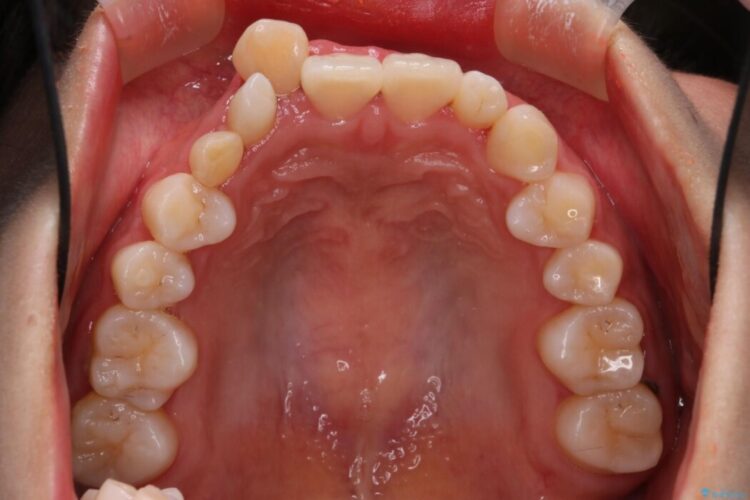

飛び出た上顎右側の八重歯が気になるとのことで来院されました。

上顎右側に乳歯が残っていることによって不正歯列(八重歯)となっているため、乳歯を抜歯してスペースを確保した上で、インビザラインによる八重歯の改善を行いました。